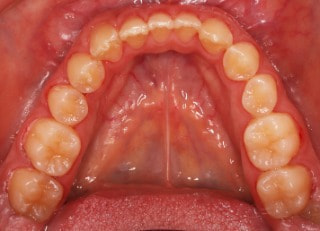

治療後(2年11ヶ月後)